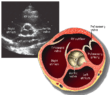

| Each figure contains a TTE with a black background, and a corresponding colored illustration. | Patrick J. Lynch and C. Carl Jaffe, Yale University, 2006. | ||||||||||

| Click on a figure to enlarge it and see some parts of the heart identified. RV, right ventricle; LV, left ventricle; RA, right atrium; LA, left atrium; TV, tricuspid valve; MV, mitral valve; AV, aortic valve; RVOT, right ventricular outflow tract; LVOT, left ventricular outflow tract | |||||||||||